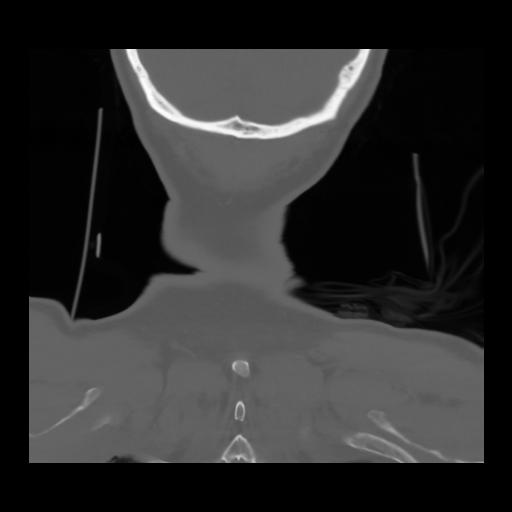

13 P.BLANDAS,,Coronal,2.000,P.BLANDAS,Coronal,